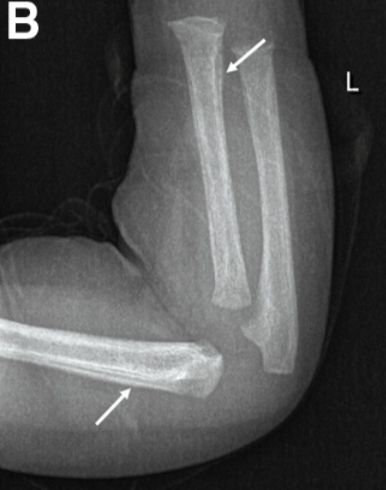

辅助检查:抗核抗体1:320,脑脊液培养阴性。肱骨、桡骨、尺骨骨皮质增厚,伴洋葱皮征(图2)。

图2 X线显示肱骨、桡骨、尺骨骨皮质增厚、洋葱皮征